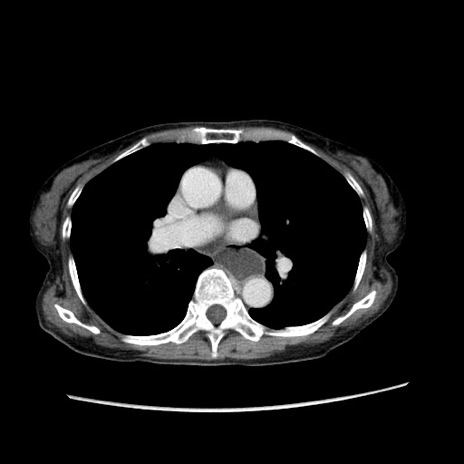

症例25(横断像)

【症例】80歳代女性

【主訴】胸のつかえ感

【現病歴】約9時間前に食後から胸のつかえた感じあり、嘔吐あり、来院。

【既往歴】胃癌(全摘)、胆摘、虫垂炎

【身体所見】心窩部に圧痛あり、反跳痛なし。

【データ】WBC 5700、CRP 0.05